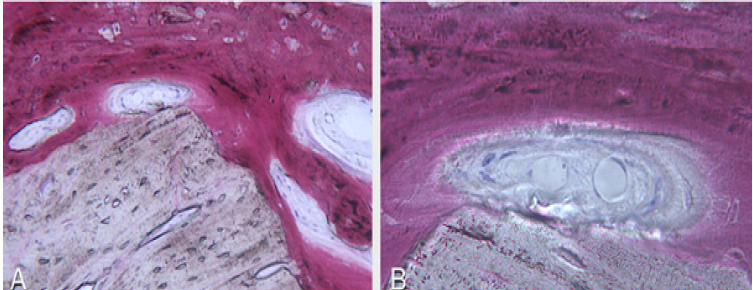

The surgery ended with 5/0 Polypropylene horizontal mattress sutures (Aragò, Barcelona, Spain). Amoxicillin 500mg every 8 hours for 7 days, Ibuprofen 600mgx3 for 3 days, Chlorhexidine 0.20% rinses morning and evening for 7 days were prescribed as postoperative medication. Postsurgical CBCT demonstrates a buccal augmentation of 4.05mm. The sutures were removed after 2 weeks of uneventful post-operative course (Figure 1-7). Six months after surgery, the clinical aspect showed an excellent volume of convex shape and hard consistency. The CBCT highlighted a horizontal gain of 4.05mm with initial mineralization. The day of re-entry the area displayed a new anatomy. The mesial implant was covered with hard tissue reproducing the shape of the cover-screw. A biopsy was taken and stored in 10% buffered neutral formalin and sent for histological examination. Healing abutments were connected and soft tissue sutured in place. After 3 months a prosthetic restoration was performed by means of a gold-ceramic screwed bridge. The histological result showed newly formed trabecular bone, in close contact with residual particles and osteoid matrix where newly formed blood vessels and active osteoblasts were present. There were not inflammatory or necrotic cells. Three years after surgery, the clinical and CBCT control show hard and soft tissue stability. The horizontal measurement of new vestibular bone is stable at 4.05mm. The peri-apical rx shows no marginal bone loss. Four years after surgery, a significant finding was observed on the new CBCT: the graft appeared almost totally reabsorbed in favor of new bone which has a radiological quality similar to that of the native bone and there is a new mature cortical plate [21] similar to the palatal native bone (Figure 8-15).

Figure 11: Courtesy of Prof. Giovanna Iezzi (University of Chieti-Pescara) A. 100x: Particle of residual biomaterial in close contact with new mineralized trabecular bone and some osteoid matrix. No necrotic and inflammatory cells. B. 200x: Particle of residual biomaterial in close contact with new mineralized trabecular bone and osteoid matrix in peripheral mineralization. Inside active osteoblasts and new blood vessels are visible.